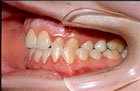

La mordida abierta anterior esquelética (Fig. 3), las sobremordidas horizontales de más de 6mm. (Fig. 4), una distancia mayor de 4mm. desde relación céntrica a máxima intercuspidación, mordida cruzada unilateral (Fig. 5 y 6) y ausencia de sectores posteriores de 5 ó más piezas, han sido los factores oclusales que se han asociado con grupos de diagnóstico específicos en disfunción de la ATM.

Fig. 3 Mordida Abierta

Fig. 4 Resalte

Fig. 5 Mordida Cruzada

(Vista Lateral)

Fig. 6 Mordida Cruzada

(Vista Frontal)